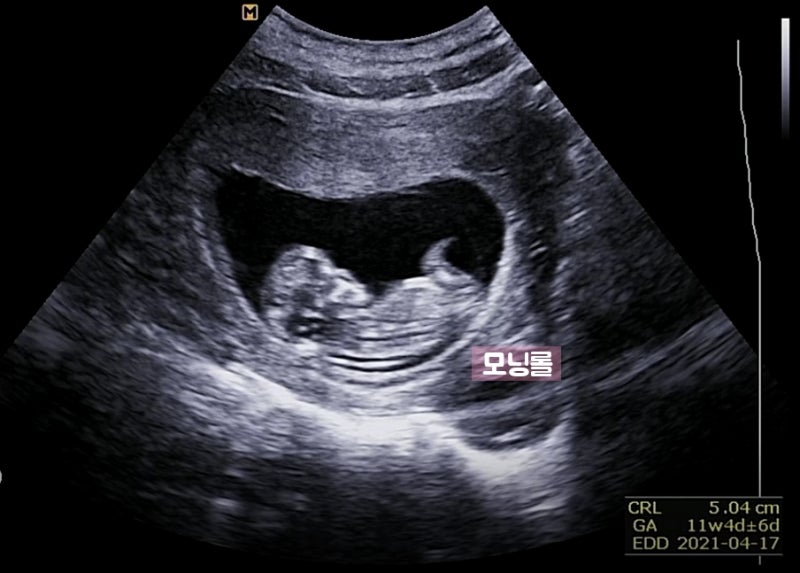

1.1차 정밀초음파&통합선별검사 임신 12주차는 중요한 시기로 아이가 많이 커져 배 초음파가 가능해져 1차 정밀초음파검사와 통합선별검사를 하게 됩니다.

정밀초음파는 1차(10~13주), 2차(20~21주)에 시행되는데, 1차 정밀초음파 검사: 태아목 투명대(NT) 두께 측정으로 태아의 염색체, 심장에 이상이 있는지 확인합니다.보통 2.5mm 미만이 정상입니다(목투명대란 아기를 둘러싼 차양막에서 목까지의 빈 부분입니다.)